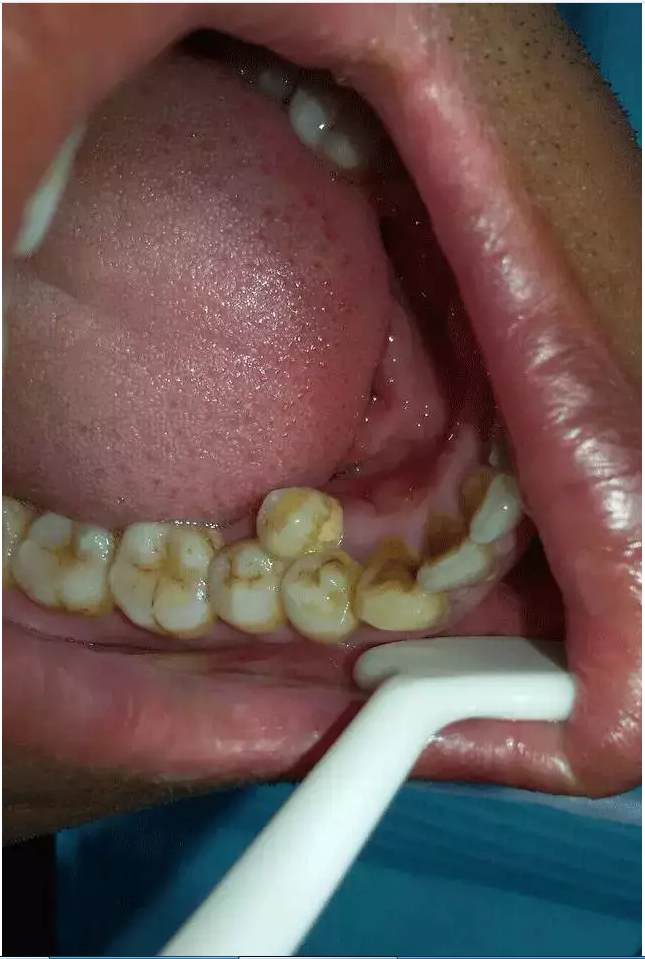

患者 男 45歲,因左上后牙疼痛就診!

檢查:左上34之腭側(cè),見一多生前磨牙,牙合面齲壞,I度松動(dòng),對(duì)側(cè)未見多生牙。

右下45之舌側(cè),可見一多生前磨牙。對(duì)側(cè)未見多生牙!

綜合分析,沒有保留價(jià)值,拔除!

如下圖: